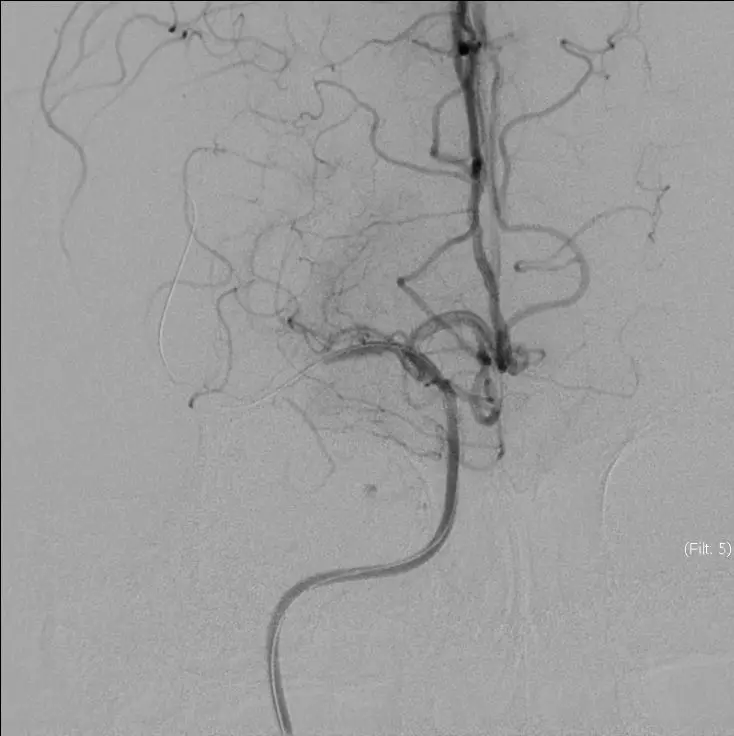

立即DSA(08-03日 13:24分)

5MIN后

5MIN后

赛诺 2.0*15mm球囊扩张

5MIN后

赛诺 2.0*15mm球囊扩张

5MIN后

10MIN后

再次与家属沟通病情,交代支架植入风险,家属表示理解,准备支架解脱

5MIN后

再次观察10MIN后

16:30分

手术结束